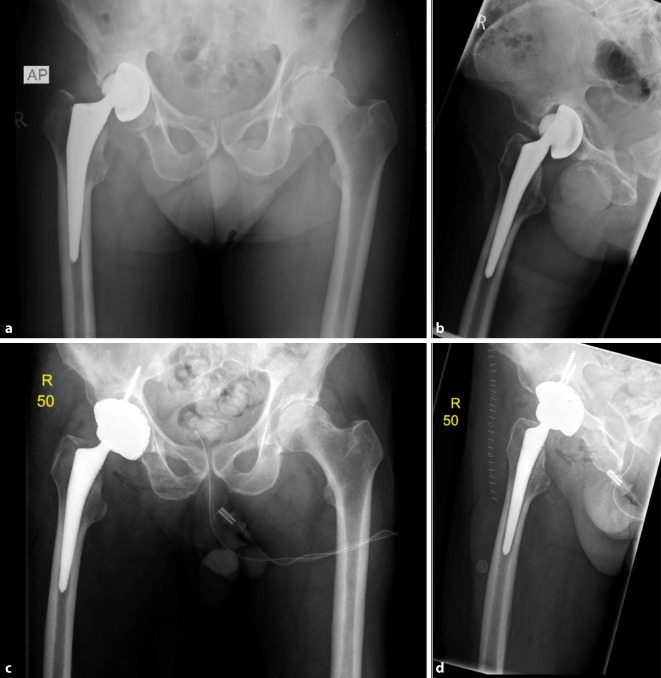

Fig. 3.

AP X‑ray of the hip (a) and axial view (b) of a 78-year-old male patient with cup loosening, type II acetabular bone defect; X‑ray of the hip AP (c) and axial view (d) after treatment with a cementless press-fit acetabular revision cup with additional screw fixation (cranial cup, AQ Implants) (Courtesy of the Department of Diagnostic and Interventional Radiology, University Hospital of Leipzig, all rights reserved)

Fig. 4.

AP X‑ray of the hip (a) and axial view (b) of an 81-year-old female patient with cup loosening, type III acetabular bone defect; X‑ray of the hip AP (c) and axial (d) after treatment with an acetabular revision cup-cage component and allogenic cancellous bone (cup-cage, Peter Brehm GmbH) (Courtesy of the Department of Diagnostic and Interventional Radiology, University Hospital of Leipzig, all rights reserved)